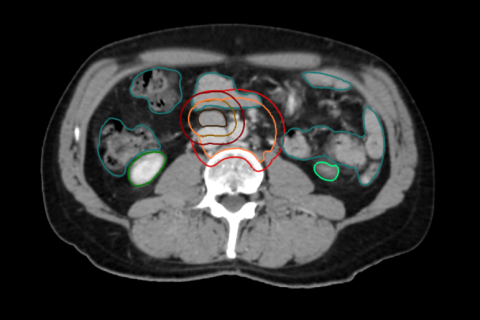

Radiothérapie ciblant un ganglion unique et épargnant les tissus sains avoisinants:

testis.png